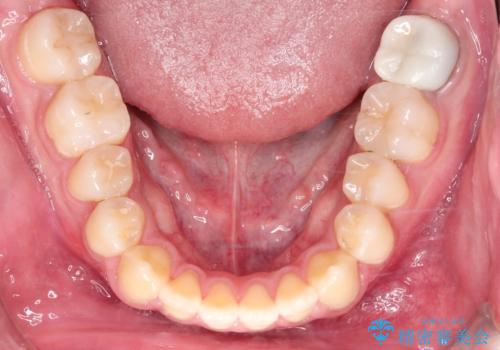

【ワイヤー矯正】前歯の凸凹を治したい。

- 前歯の凸凹を主訴に来院されました。

患者様がマウスピース矯正の使用時間に不安があるため、ワイヤー矯正にて治療を行なっております。

ワイヤー矯正は使用時間の制約がないため、マウスピースの装着管理が苦手な人には向いています。